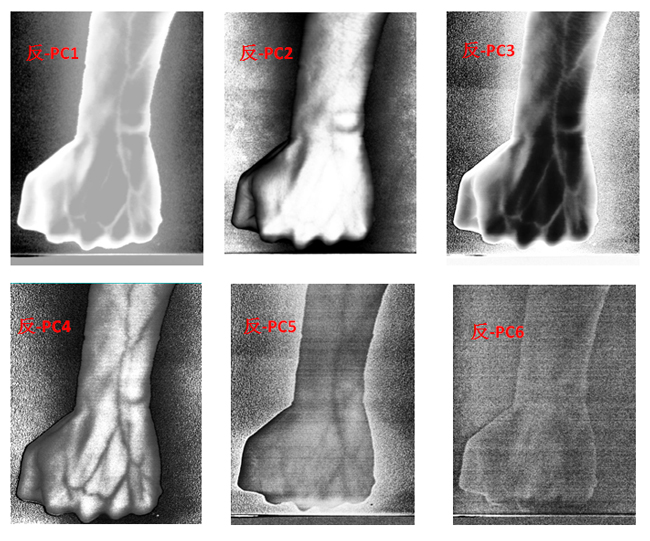

为了客观地识别手臂上的静脉,对经预处理后的高光谱数据进行主成分分析(Principal Component Analysis, PCA),去除波段之间的多余信息、将多波段的图像信息压缩到比原波段更有效的少数几个转换波段下。图9为手臂正反面经PCA变换后的前6个主成分。

图9 手臂正反两面PCA处理后的前6个主成分

为了更客观真实地识别出手臂静脉,根据波段组合的特点,对PCA前六个主成分组合成各种假彩色图像,如图10为手臂正面的假彩色合成图像,图11为手臂反面的假彩色合成图像。与灰度图相比,假彩色合成更能直观地识别出手臂静脉。

图11 手臂反面PCA假彩色合成图像